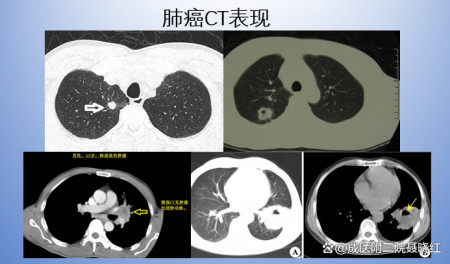

2、胸部CT CT是临床中最常见的检查方法,具有更高的分辨率,可发现微小病变和普通X线胸片难以显示的部位。增强CT能敏感地检测出肺门及纵隔淋巴结肿大,有助于肺癌的临床分期。